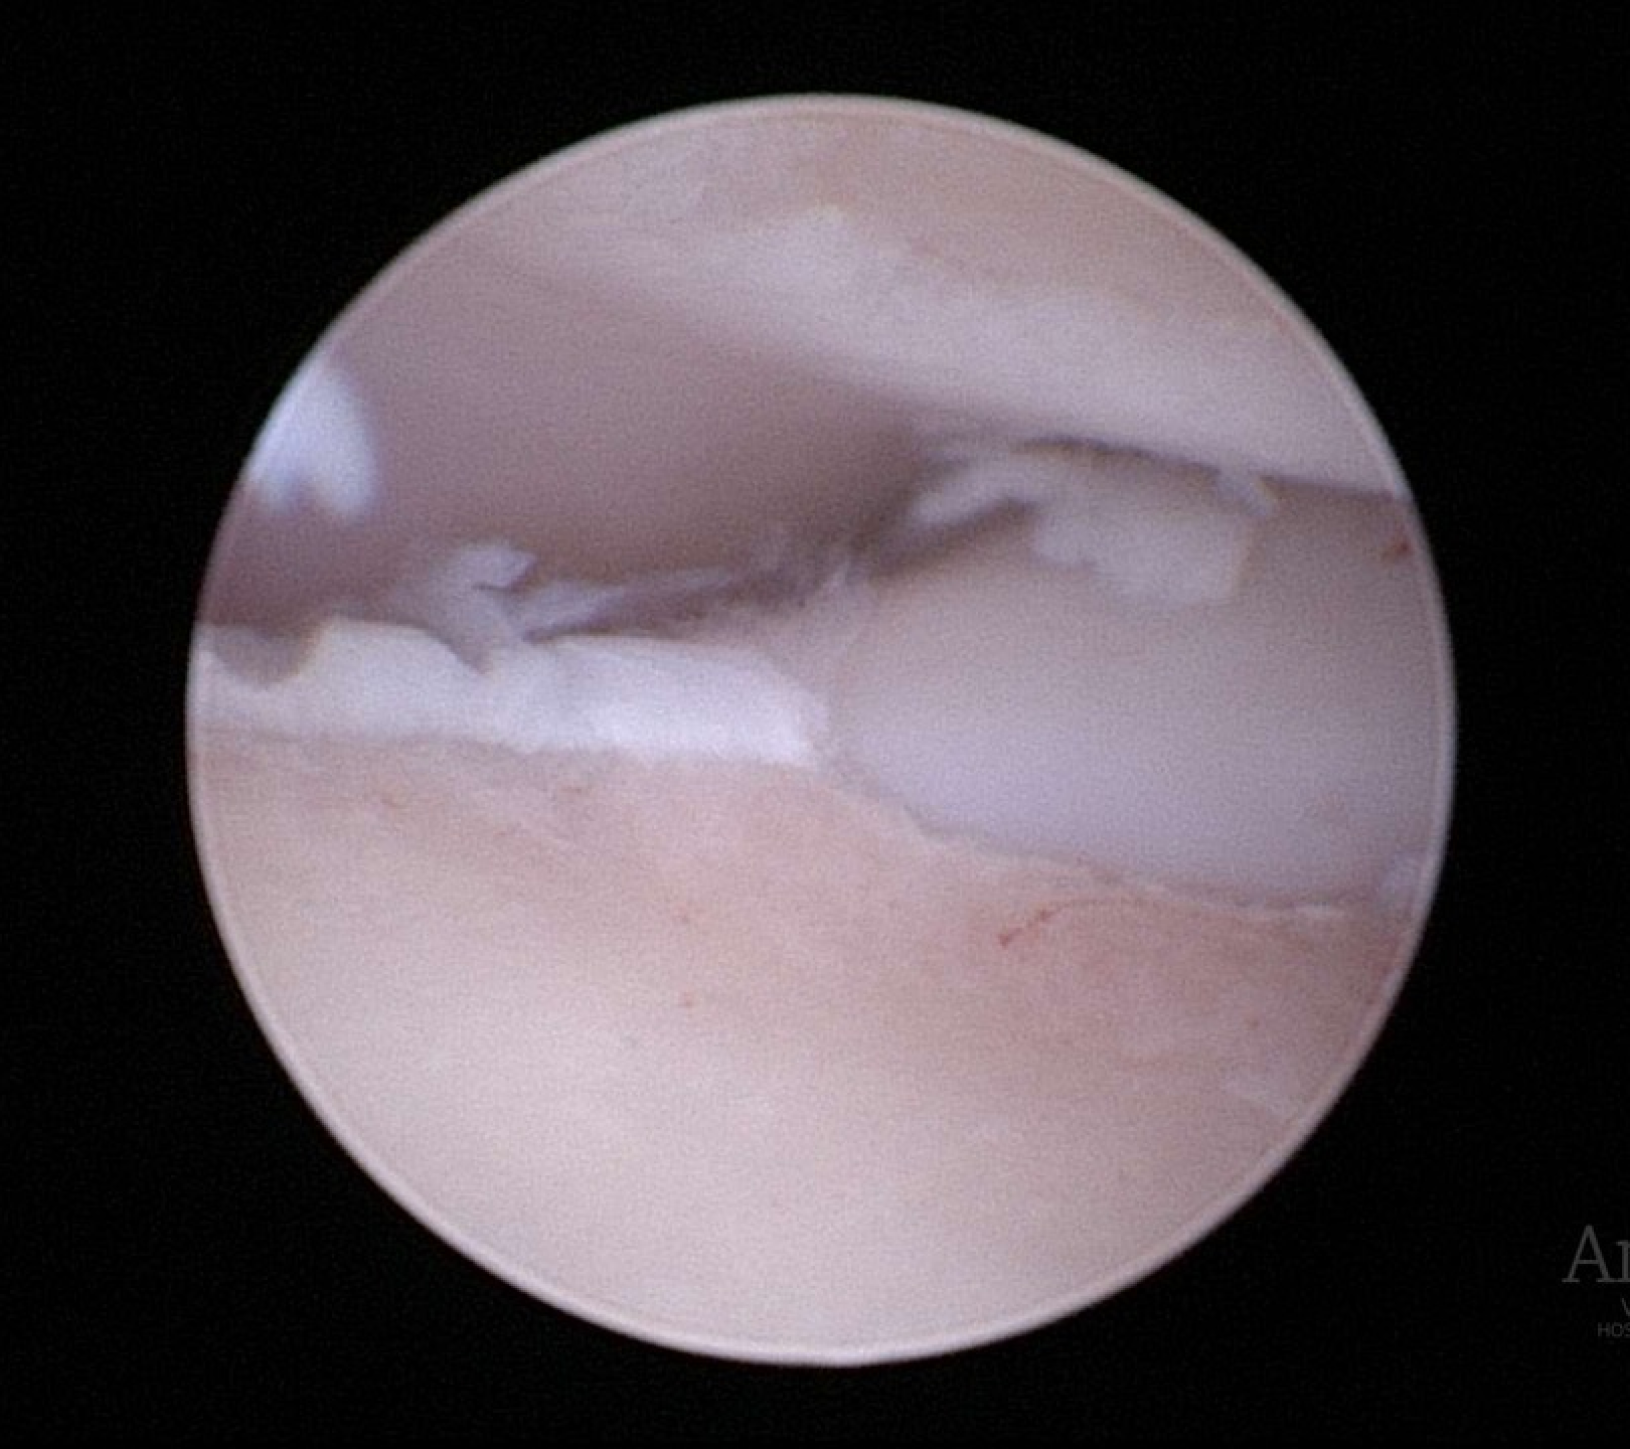

La artroscopia (introduciendo una pequeña cámara dentro de la articulación) supone un apoyo diagnóstico al TAC, ya que permite visualizar el cartílago articular (cosa que no hace el anterior). Al mismo tiempo permite tratar la mayoría de lesiones asociadas a la patología (retirar fragmentos, etc.)

• RETIRADA DEL FRAGMENTO: La retirada de los fragmentos libres de cartílago y hueso puede reducir las molestias articulares. Ésto se puede llevar a cabo bien utilizando un artroscopio (técnica artroscópica) o mediante artrotomía (abordaje quirúrgico convencional a la articulación mediante una incisión). Actualmente es más habitual emplear el primer método pues se trata de una técnica de mínima invasión, donde entre otras ventajas, se consigue una recuperación más rápida en la mayoría de casos. Desafortunadamente la cojera puede llegar a no mejorar en algunos pacientes, siendo atribuible en muchas ocasiones a la presencia de incongruencia articular y / o una osteoartritis avanzada.

• Enfermedad del proceso coronoides medial (EPCM): se trata de la condición más encontrada de todas las que se incluyen en la displasia de codo. El proceso coronoides puede encontrarse malformado, fisurado e incluso fragmentado. Como resultado de esta enfermedad y del roce anormal de dicha estructura con la superficie articular del cóndilo humeral medial, se produce un desgaste acelerado de las superficies cartilaginosas del aspecto medial del codo dando lugar al Síndrome del compartimento medial, el cual se ve favorecido por la sobrecarga que soporta la región interna de la articulación en condiciones fisiológicas.